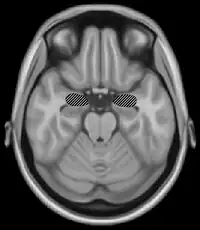

The basal ganglia are a group of nuclei which are located in the medial temporal lobe, above the thalamus and connected to the cerebral cortex. Specifically, the basal ganglia includes the subthalamic nucleus, substantia nigra, the globus pallidus, the ventral striatum and the dorsal striatum, which consists of the putamen and the caudate nucleus.[8] The basic functions of these nuclei deal with cognition, learning, and motor control and activities. The basal ganglia are also associated with learning, memory, and unconscious memory processes, such as motor skills and implicit memory.[4] Particularly, one division within the ventral striatum, the nucleus accumbens core, is involved in the consolidation, retrieval and reconsolidation of drug memory.[9]

The caudate nucleus is thought to assist in learning and memory of associations taught during operant conditioning. Specifically, research has shown that this part of the basal ganglia plays a role in acquiring stimulus-response habits, as well as in solving sequence tasks.[8]

Damage to the basal ganglia has been linked to dysfunctional learning of motor and perceptual-motor skills. Most disorders that are associated with damage to these areas of the brain involve some type of motor dysfunction, as well as trouble with mental switching between tasks in working memory. Such symptoms are often present in those who suffer from dystonia, athymhormic syndrome, Fahr's syndrome, Huntington's disease or Parkinson's disease. Huntington's and Parkinson's disease involve both motor deficits and cognitive impairment.[8]